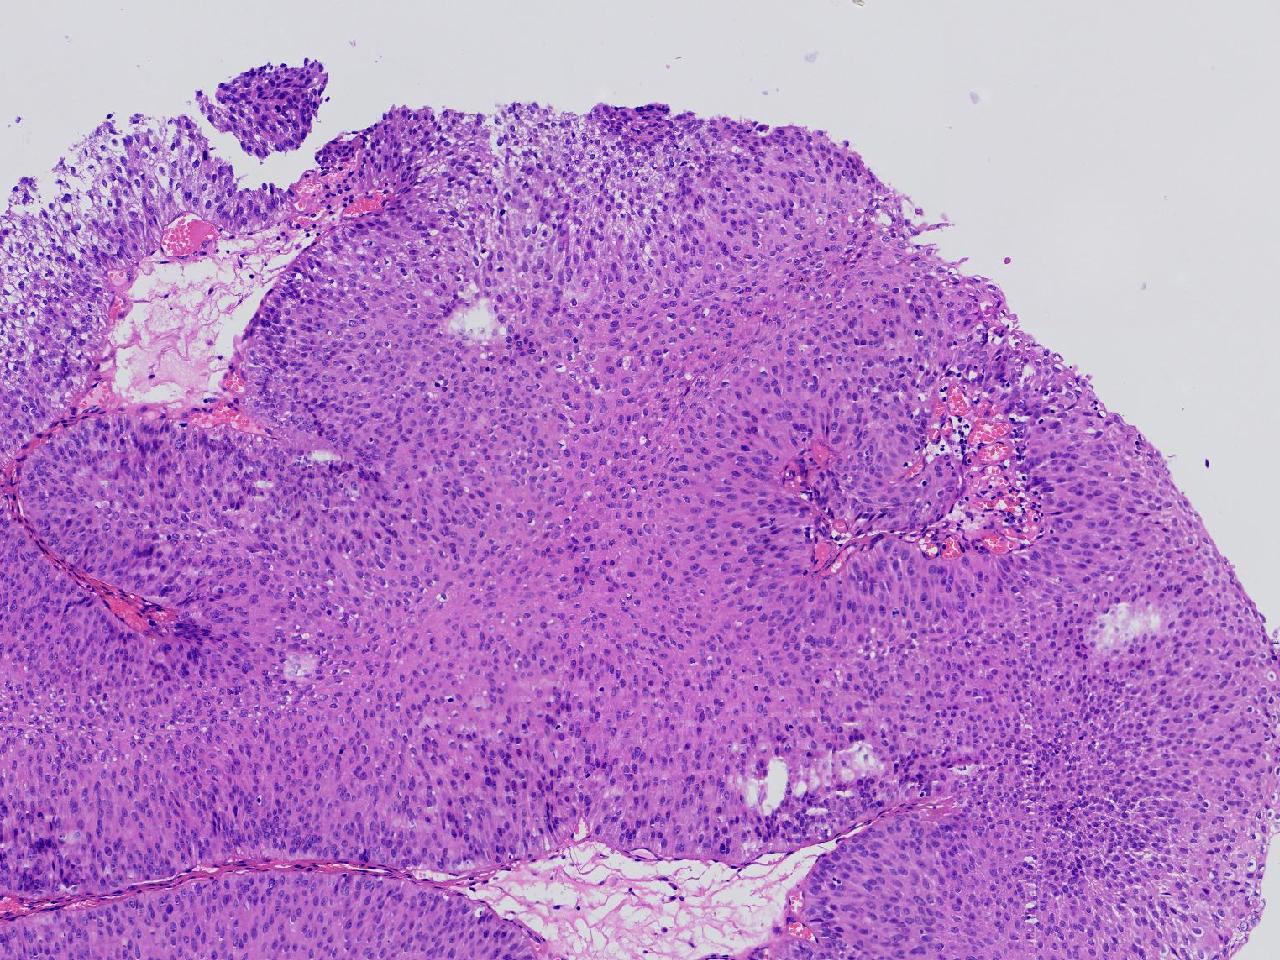

男,79岁,膀胱肿物。

膀胱肿物

灰白色不整形软组织多块,2X1X1厘米。

考虑:乳头状尿路上皮癌

考虑低级别,非浸润。

乳头状尿路上皮癌,低级别。

这几张图片上没有看到明确的浸润。